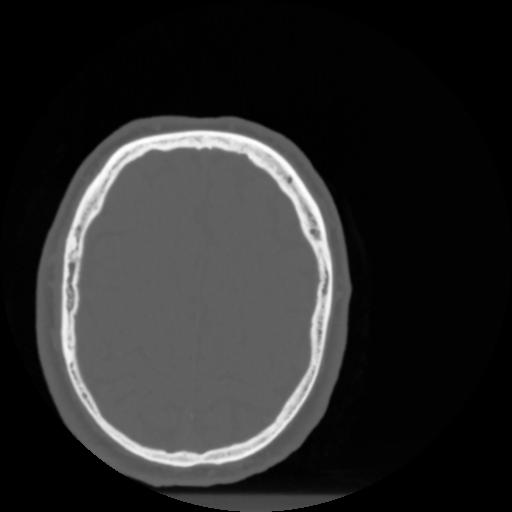

4 CEREBRO,,Vol,0.5,CEREBRO,,